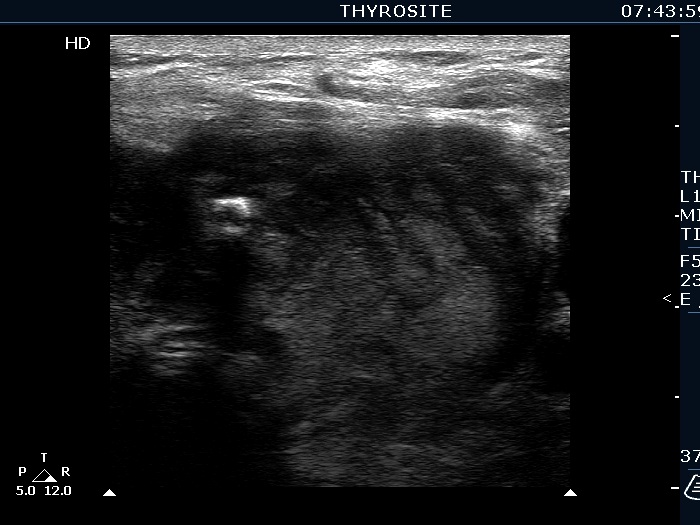

Ultrasonography. The right lobe was echonormal and presented several hypoechoic nodules. A large, inhomogeneous, partly deeply hypoechoic, partly minimally hypoechoic or echonormal mass occupied the left lobe. The borders of the tumor were irregular. There were multiple lymph nodules upper and lateral to the left thyroid lobe. The nodes had a heterogeneous pattern and lacked hilum. The vascularity was scanty both in the thyroid nodules and the lymph nodes.